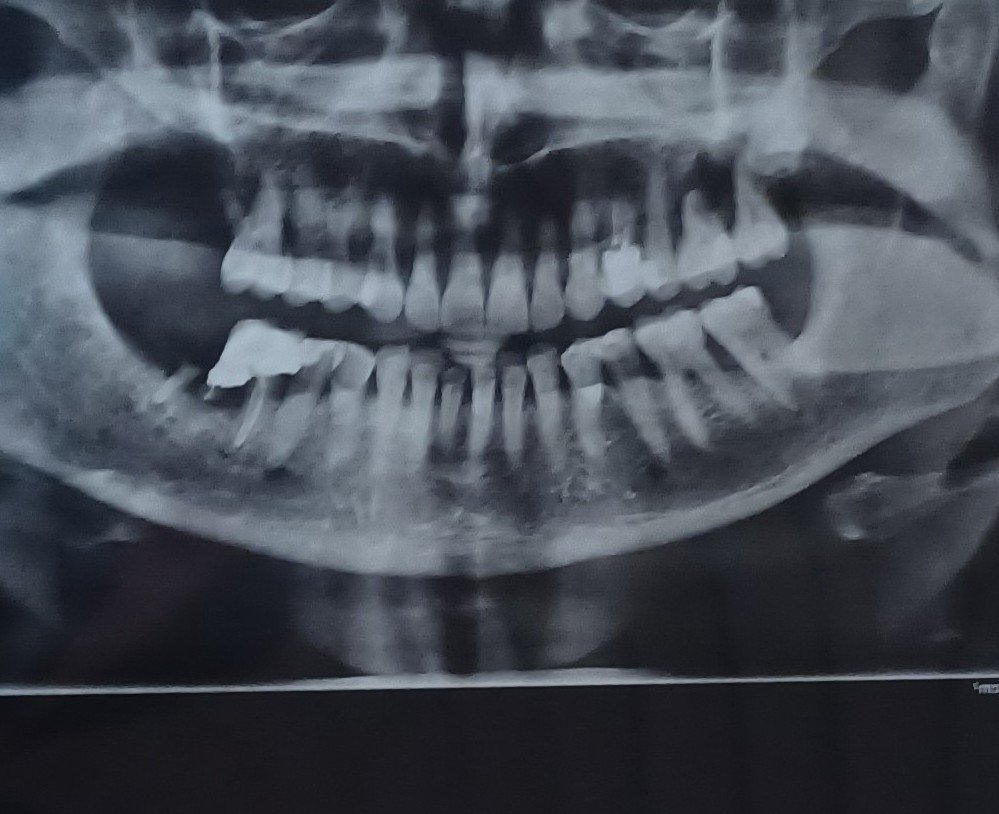

Зависи колко е костта, ако имате снимка можете да я прикачите или да я изпратите на лично съобщение.

За горе вляво говорим, нали? Защото 7ми зъб има вляво, а вдясно няма (освен, ако не е обърната снимката). Честно казано не се вижда добре, ако можете да снимате само зъбите, които за проблемни. Просто не мога да видя нивото на костта заради лошото качество.